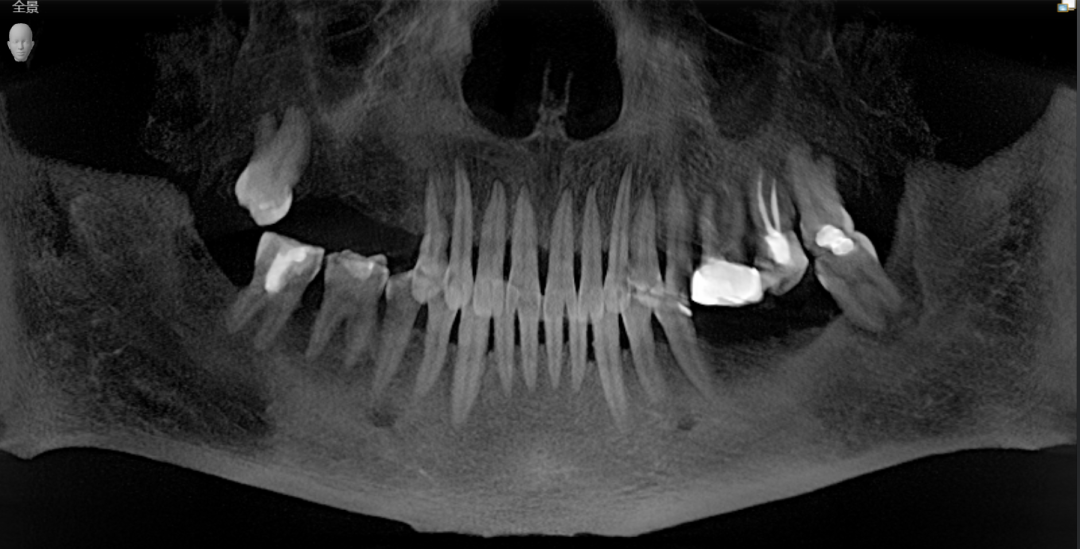

阿姨术前口内CBCT全景照

曹申主任为阿姨进行了数字化的会诊,借助Sirona CBCT全景影像信息和相关修复信息为基础,借助数字化专业种植设计软件进行术前诊断和种植方案规划。